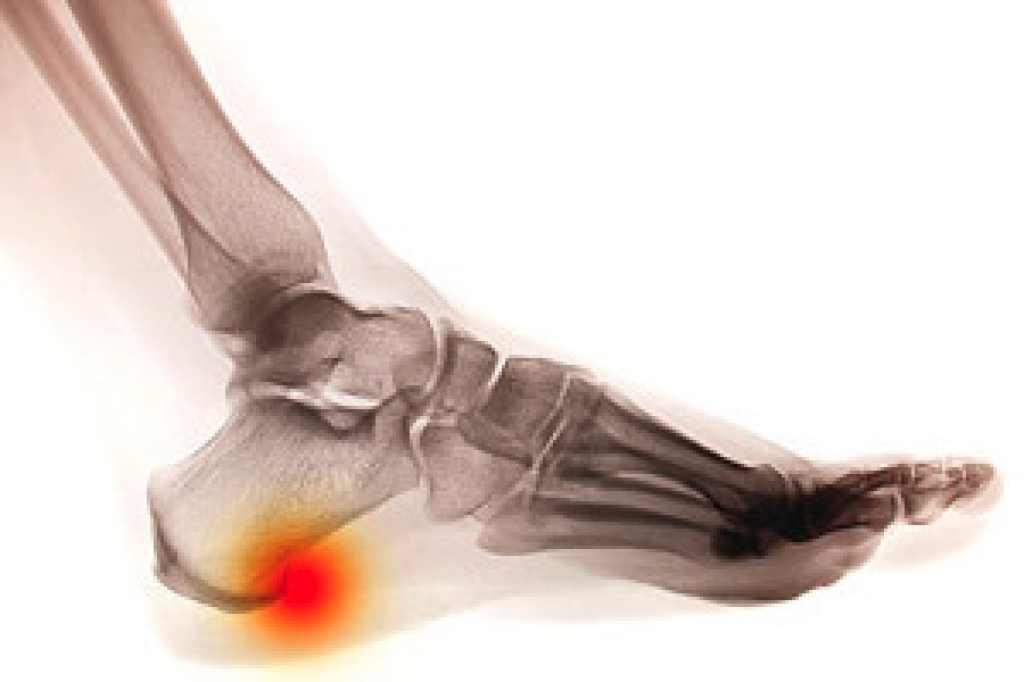

Athlete’s foot initially occurs as a rash between the toes. However, if left undiagnosed, it can spread to the sides and bottom of the feet, toenails, and if touched by hand, the hands themselves. Symptoms include:

Diagnosis is quick and easy. Skin samples will be taken and either viewed under a microscope or sent to a lab for testing. Sometimes, a podiatrist can diagnose it based on simply looking at it. Once confirmed, treatment options include oral and topical antifungal medications.